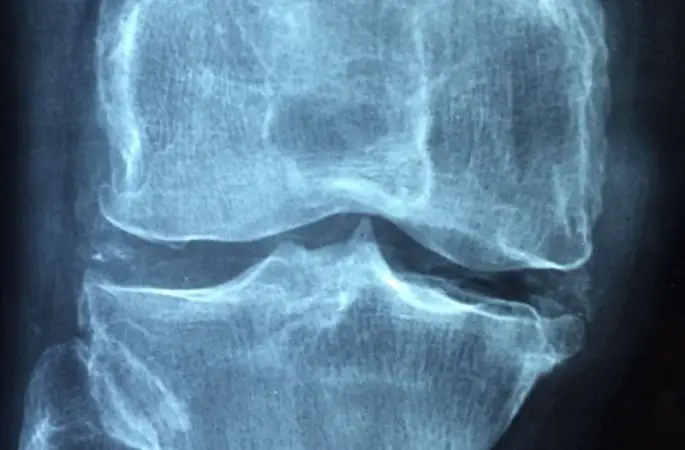

Op. Dr. Mesut Bolat, kök hücrenin aslında anaç bir hücre olduğunu, bulunduğu veya verildiği her dokuya dönüşebilme özelliğine sahip olan önemli bir doku olduğunu kaydederek, “Eklemlerde meydana gelen kıkırdak hasarları tamir edilerek onarılması kök hücre tedavisi ile mümkün. Günümüzde son derece popüler olan kök hücre tedavisi sayesinde kıkırdak gibi üretilmesi ve inşası zor olan dokuların yeniden yapılanma sürecinde farklı tedavi yöntemleri hastalara şifa oluyor” diye konuştu.

Şiddetli eklem ağrısı şikayetleri olan ancak cerrahi için erken veya ameliyat olmaktan çekinen ortopedi ve travmatoloji hastalarında, kireçlenme sürecinin ilerlememesi ve kıkırdakların daha hızlı iyileşmesini sağlamak için kök hücre tedavisine başvurulduğunu anlatan Dr. Bolat, “Bu tedavi şekli, kas, bağ ve menisküs yırtıkları gibi şikayetlerde etkili bir yöntem olarak öne çıkmaktadır. Bu yüzden etkili bir yöntem olarak tercih edilir” diye konuştu.